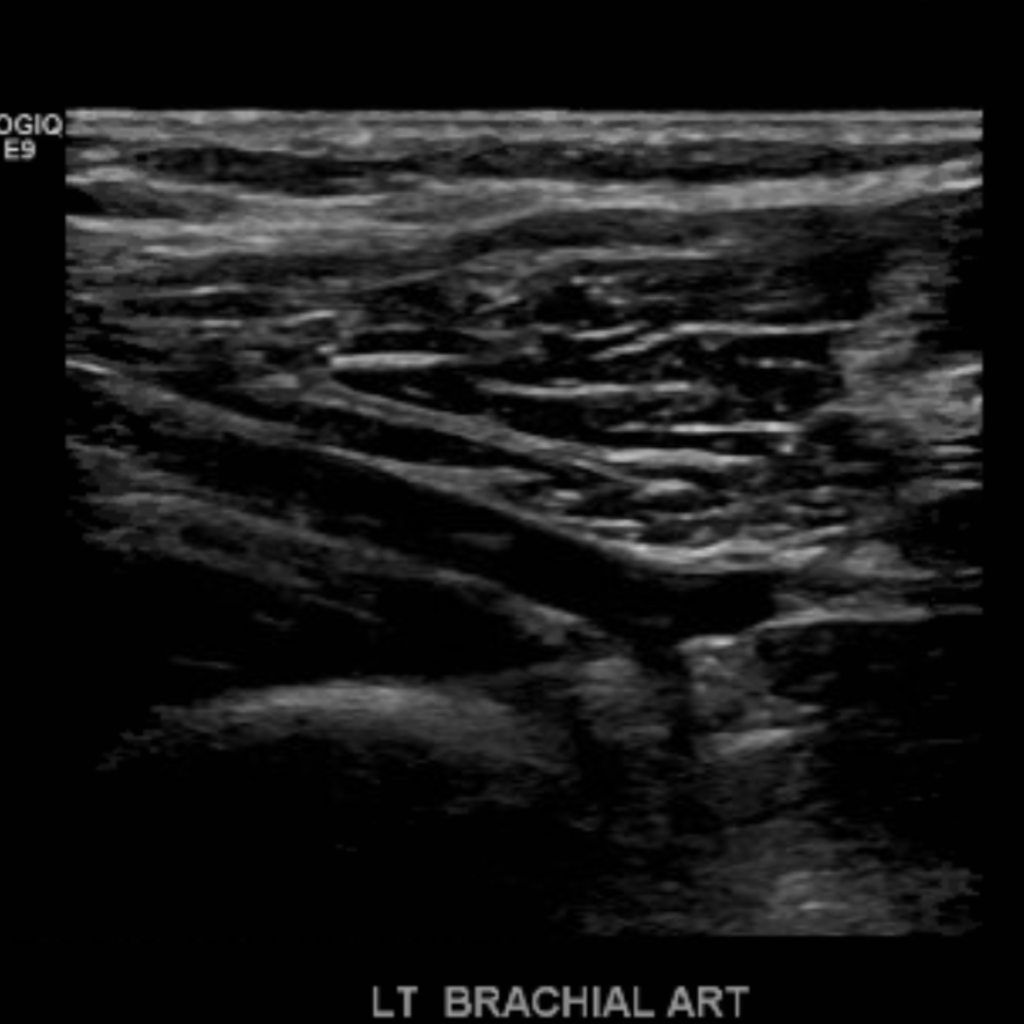

The subclavian artery arises from the brachiocephalic artery on the right and off of the aortic arch on the left. This artery further divides into the axillary, brachial, radial, ulnar, palmar and digital arteries respectively.